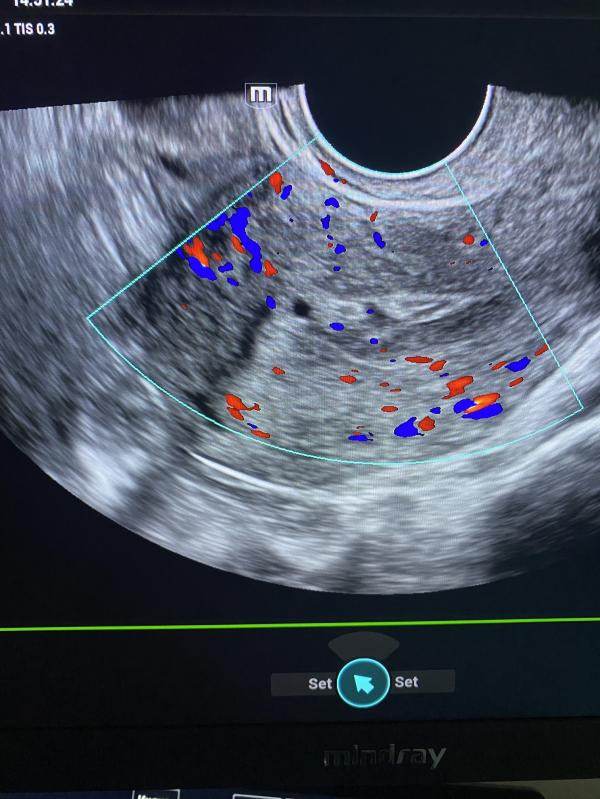

Объясните пожалуйста, вот почему женщина может кровить и ходить на Узи, где ей каждый раз специалист выносит в заключении полип.

Рекомендации : посетить гинеколога, для удаления полипов.

В яичниках полипов не бывает, возможно фибромы ( плотные образования) и различной структуры кисты. Тактика ведения при образованиях в яичниках различная: от наблюдения до оперативного лечения